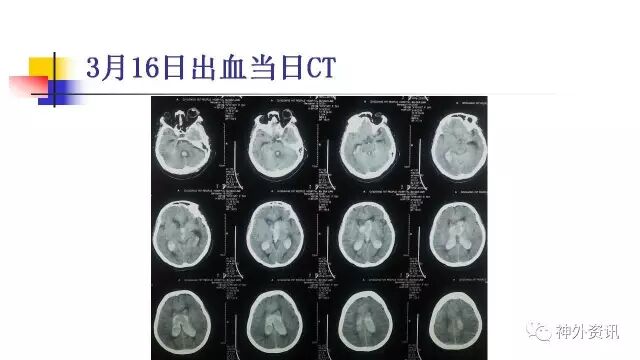

今天为大家分享的是《正海-妙术视界》第三十九期,由哈尔滨医科大学附属第一医院神经外科三病房主任史怀璋教授团队带来的国内首例“经静脉途径栓塞动静脉畸形”动态课件,相关文章亦已发表在2016年第12期的《International Neuroradiology》杂志,欢迎观看、阅读。